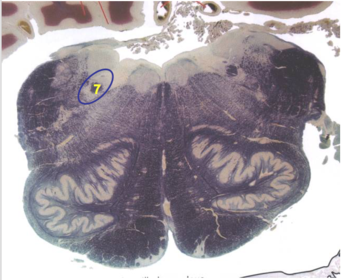

| Superior cerebellar peduncle | |

| Dentate nucleus | |

| Fastigial nucleus | |

| Anterior spinocerebellar tract | |

| Spinal nucleus of V | |

| Spinal tract of V | |

| Middle cerebellar peduncle | |

| Superior vestibular nucleus | |

| Medial lemniscus | |

| Trapezoid body | |

| Ventral trigeminothalamic tract | |

| Superior olive | |

| Longitudinal pontine fibers (corticospinal tract) | |

| Transverse pontine fibers (dark fibers) | |

| Pontine nuclei (pale) | |

| Central tegmental tract | |

| ALS | |

| Medial longitudinal fasciculus | |

| Principle nucleus of V | |

| Mesencephalic V tract | |

| Trigeminal root fibers | |

| Motor nucleus of V | |

| Cerebellar vermis | |

| Lateral lemniscus | |